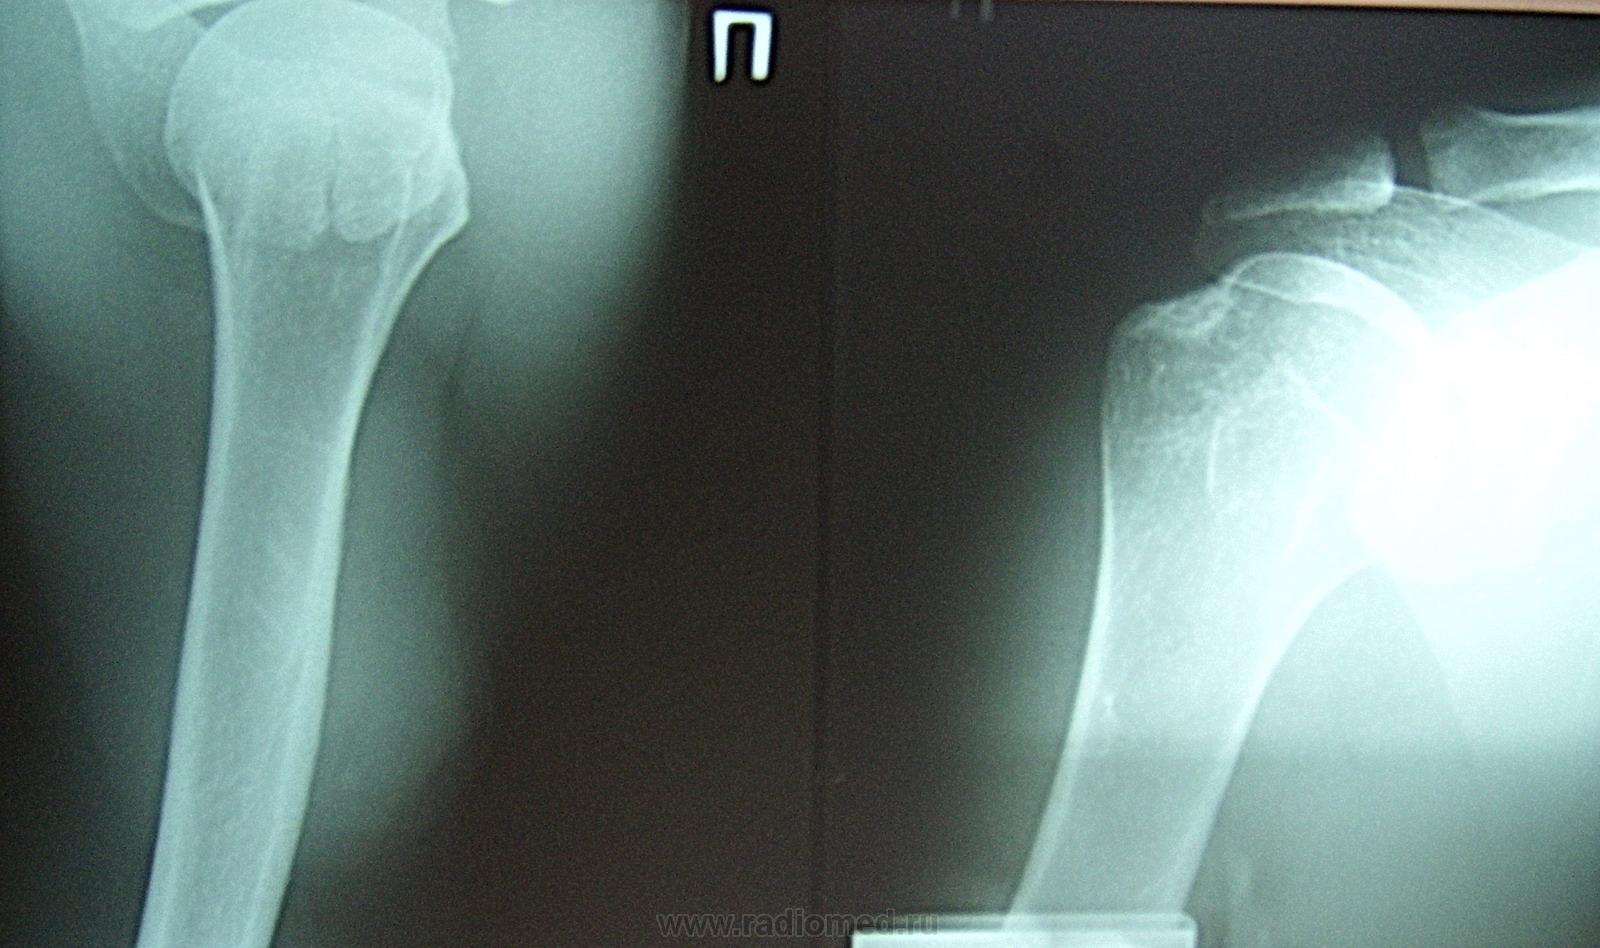

Пол пациента: Мужской пол Тип патологии: Травма Область исследования: Скелетно-мышечная система Методы исследования: Rg Мужчина упал на правую руку. Беспокоят боли, невозможно поднять руку в сторону. Прошу прощение за качество. ID:9887 Втр, 07/12/2010 - 17:14 #1 Александр Викторович Не на сайте Был на сайте: 8 лет 4 часа назад Зарегистрирован: 31.07.2010 - 13:05 Публикации: 639 Игорь Артурович, перелома не видно, вероятно травма мягкотканная. Втр, 07/12/2010 - 19:28 #2 Глазков Игорь А... Не на сайте Был на сайте: 9 месяцев 1 неделя назад Зарегистрирован: 19.12.2008 - 20:41 Публикации: 1597 акромион не повреждён? Прийди к Себе Втр, 07/12/2010 - 20:25 #3 Александр Викторович Не на сайте Был на сайте: 8 лет 4 часа назад Зарегистрирован: 31.07.2010 - 13:05 Публикации: 639 я думаю это вариант развития. о таком строении акромиона пишет Королюк. Втр, 07/12/2010 - 20:33 #4 Глазков Игорь А... Не на сайте Был на сайте: 9 месяцев 1 неделя назад Зарегистрирован: 19.12.2008 - 20:41 Публикации: 1597 комментарий. Прийди к Себе

Игорь Артурович, перелома не видно, вероятно травма мягкотканная.

акромион не повреждён?

я думаю это вариант развития. о таком строении акромиона пишет Королюк.